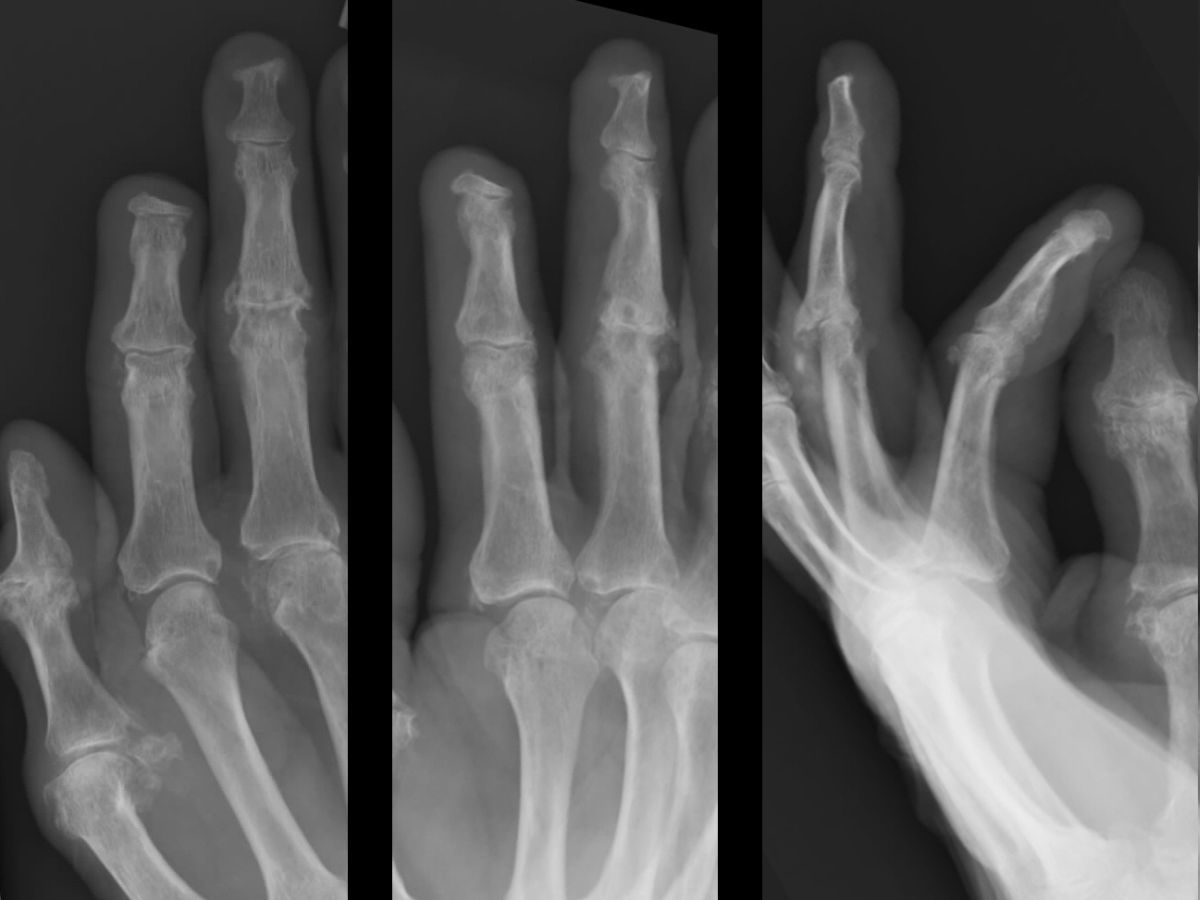

| Case

4. A dog bit off this young man's index fingertip. Although the PA Xray looks as though the bone was kept, additional views show an amputation through the tuft. |